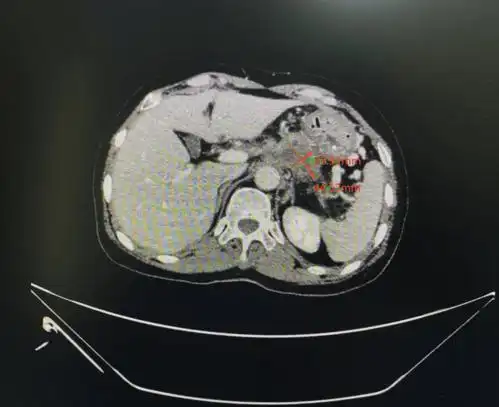

【抗癌故事-晚期胰腺癌】身上被放置五根引流管痛苦续命,钱祝银主任

纳米刀治疗晚期胰腺癌